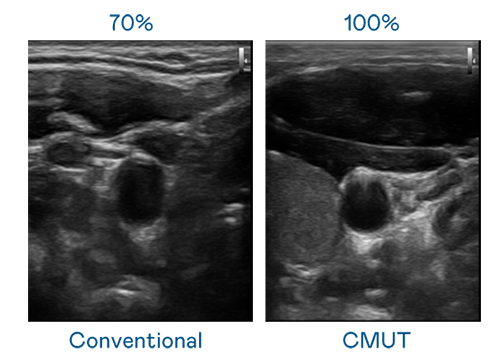

CMUT 技术是一种用电容式微机电元件来产生超音波讯号的技术。与传统 PZT 压电式技术相比,CMUT 频宽增加 30%,更宽频的超音波讯号让影像解析度大幅提升,是实现高影像品质医疗超音波扫描、促进精准医疗发展的关键技术。

大频宽带来超清晰影像

超音波影像的解析度高低,首先取决于探头能发出的讯号频宽。腾博会 CMUT 可提供高清晰的超音波讯号,提供高频宽、高灵敏度、影像纹理细节更高的超音波影像,协助医护人员缩短影像判读时间及利用精准的医疗影像进行诊断。